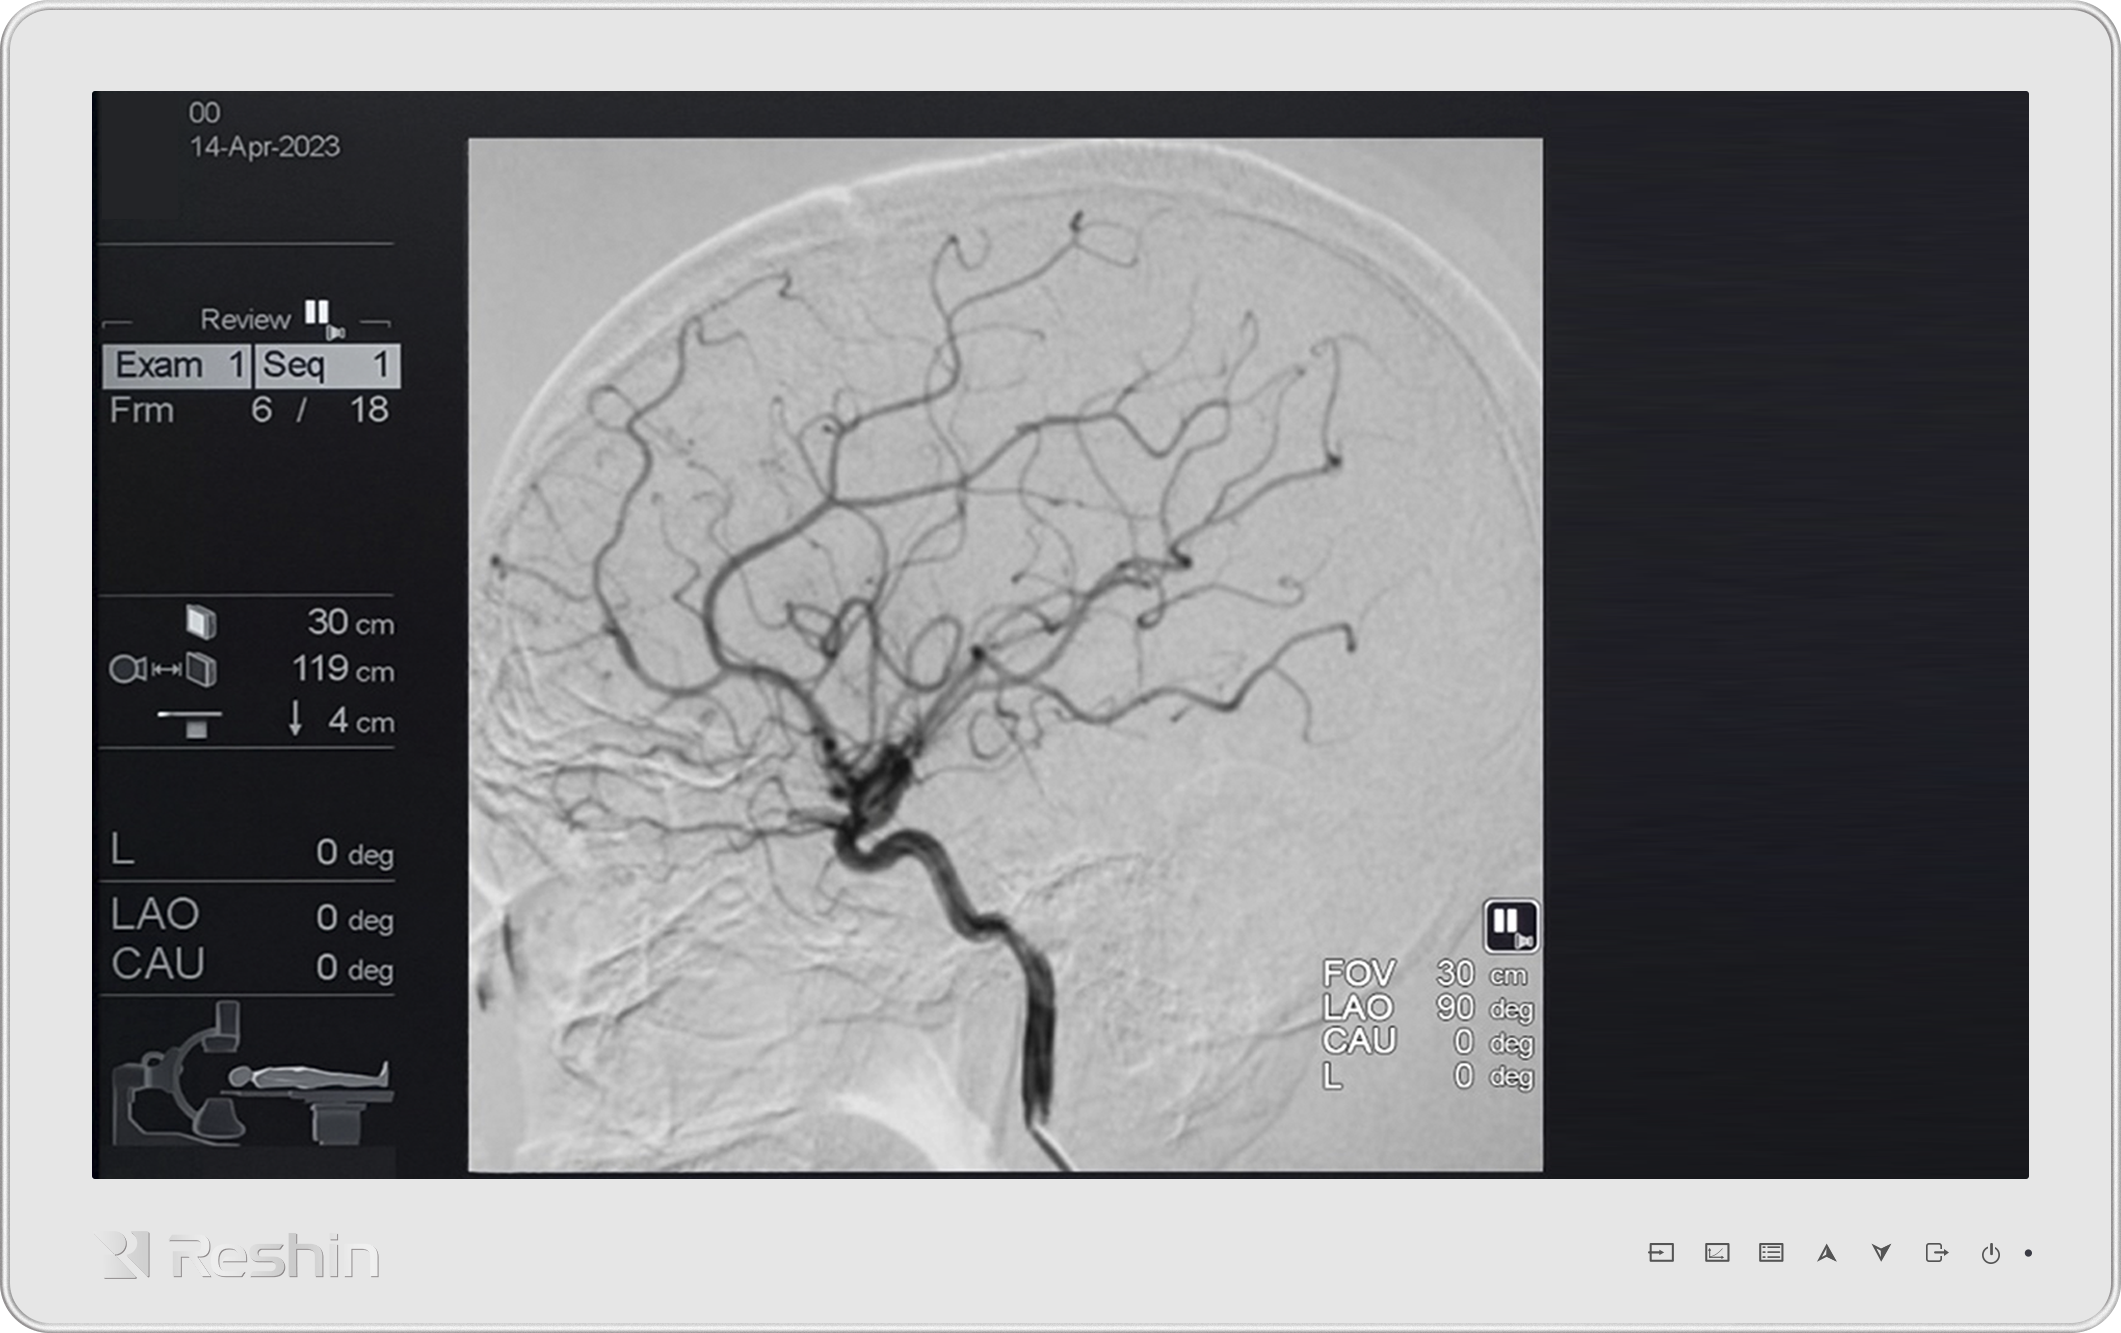

外科手术显示器的稳定运行,依赖核心技术与标准支撑。主流技术分为两类:LCD(液晶显示器)通过背光层与液晶分子控制光线成像,成本较低且亮度稳定,适合常规外科手术;OLED(有机发光二极管显示器)无需背光,能实现像素级控光,色彩还原更细腻、响应速度更快,在神经外科等对细节要求极高的场景中优势显著。同时,所有医疗级显示器都需符合DICOM 标准,该标准通过校准亮度、对比度等参数,确保 X 光、CT 等影像显示与原始数据一致,避免因显示偏差导致诊断误差。

在应用场景上,外科手术显示器用途广泛。在腹腔镜、关节置换等手术中,它实时传输内镜影像,帮助医生避开关键器官;在影像诊断环节,为 CT、MRI 影像解读提供高清显示;在远程医疗领域,通过高清传输技术,让异地专家实时参与手术指导,打破空间限制。